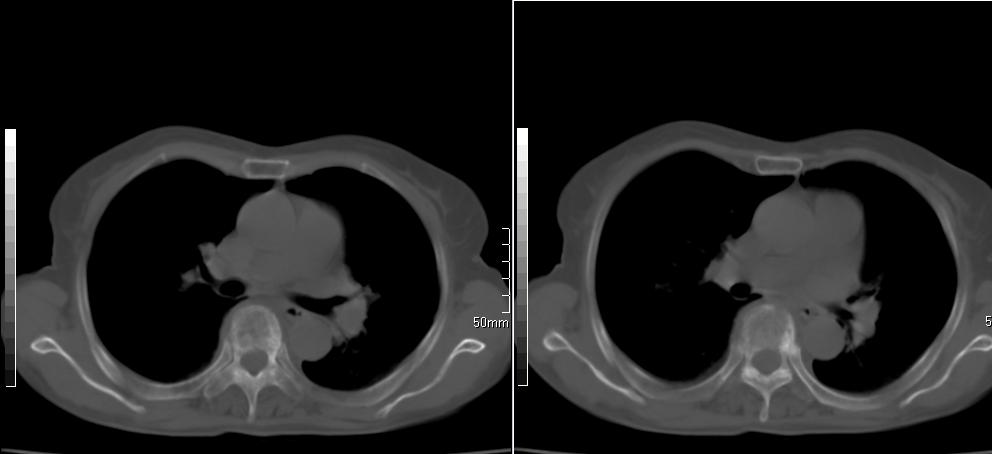

标题: CT26857:女,60岁,胃部不适前来就诊,不咳嗽,乏力,胸椎 [打印本页]

标题: CT26857:女,60岁,胃部不适前来就诊,不咳嗽,乏力,胸椎

1、胸椎有骨质破坏伴周软组织,考虑胸椎转移。2、考虑左肺中央型肺癌可能。

椎体有高密度影,多系转移。

支持中央型肺癌,胸椎转移。

1)考虑左肺中央型肺癌。2)胸椎转移瘤不排除;建议行mri检查。

左肺中央型肺癌,胸椎大致正常,必要时ect扫描